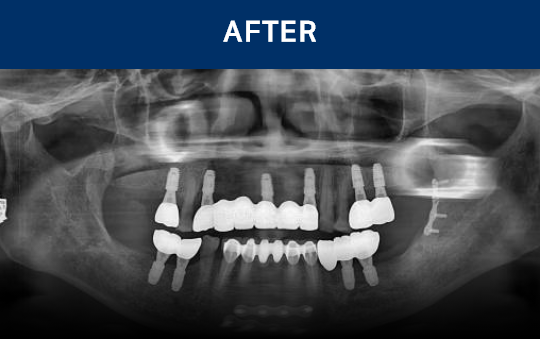

种植牙是在精准诊断与治疗计划的基础上,

通过多个步骤进行的治疗方式

会根据患者的口腔状况, 分阶段安全推进

考虑骨骼状态与神经位置,

制定种植位置与手术计划

种植牙是一项高难度治疗,

需依赖精密检查与充分的术前计划

因此, 选择具备丰富经验与专业技术的

医疗团队尤为重要